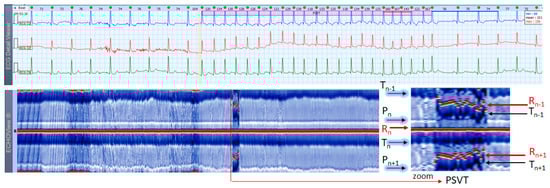

3.5. Paroxysmal Supraventricular Tachycardia Cases

This section interprets 3-lead Holter ECG strips and the corresponding ECHOView images (ECG lead 1) of three patients presenting short runs (≤10 s) of paroxysmal supraventricular tachycardia (PSVT) at the background of predominant NSR for most of the record (Figure 10, Figure 11 and Figure 12). These arrhythmias could occur at any age and are more common among women. The ‘slow-fast’ AVNRT is the most common form of PSVT, particularly in otherwise healthy hearts. It is caused by a reentrant circuit, created between two pathways (‘slowly’ and ‘fast’ conducting pathways) in or around the AV node. When the HR is too high, it is sometimes difficult to differentiate PSVT from high-rate SINT, especially in people without underlying cardiac or non-cardiac diseases. In patients with overt cardiac diseases or other pathological conditions (for example hyperthyroidism), PSVT must be differentiated not only from sinus tachycardia (common in such conditions) but also from high-rate AFL/AF. ECHOView color maps in such cases present quite distinctive patterns of PSVTs compared to NRS and SINT (Figure 6, Figure 7 and Figure 8). The beginning and the end of the arrhythmia can be identified at a glance (Figure 10, Figure 11 and Figure 12). In addition, ECHOView may facilitate the differentiation of the different PSVT subtypes. In summary, ECHOView improves the reading of Holter recordings with PSVT by saving time to visually locate the arrhythmia episodes and refine the diagnosis of these typically short events.